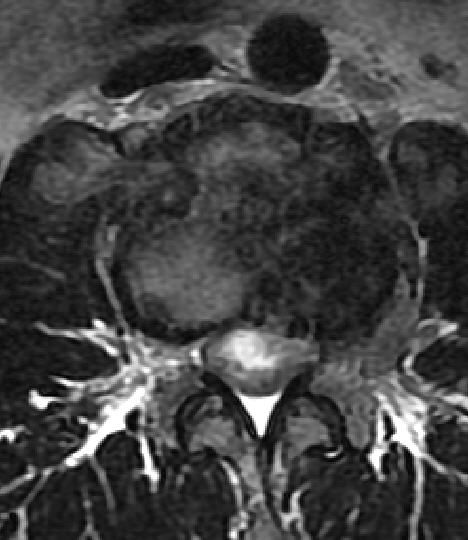

CT

CT可清楚地显示椎管横断面的骨性结构,对侧隐窝狭窄,黄韧带肥厚,椎间小关节病变及神经孔周围极外型椎间盘突出的显示有独特的临床价值,CT可提出比椎管造影更准确的鉴别诊断。CT对蛛网膜下腔观察不如脊髓造影。

MRI

可提供腰椎管的矢状面、冠状面和轴位横断面上的影像。椎管狭窄以T2加权像显示较好,脑脊液为高信号,产生所谓“脊髓造影”的效果,而骨质增生,骨赘、间盘均为低信号,能清晰地显示椎管狭窄,以及对脊髓的压迫情况。但对肥大的黄韧带、骨质增生等的判断则不如较高清晰度CT扫描。

腰椎管狭窄MRI表现。